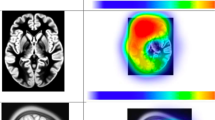

Functional Magnetic Resonance Imaging (fMRI) with Diffusion Tensor Imaging (DTI), fiber tractography and neuronavigated transcranial magnetic stimulation (nTMS) are widely employed for this purpose [182, 183]. In few centers, positron emission tomography (PET) and Magnetoencephalography (MEG) are also used, even though they are mostly applied in a research setting [184].

fMRI

Functional magnetic resonance techniques allow to establish a functional map of the eloquent regions involved in patients harboring brain tumors [185]. fMRI assesses brain activation by detecting modifications in blood oxygenation level by using the blood oxygen level-dependent (BOLD) contrast [186]. Task-based fMRI is used to localize non-invasively eloquent cortical areas [187]. Resting-state-fMRI is emerging as pre-surgical tool with automatic software for extraction of different networks at the whole brain level [188, 189]. In clinical setting, task-based fMRI compares BOLD signal changes while performing specific tasks to baseline conditions, based on the assumption that increased cerebral blood flow reflects neuronal and synaptic activity [190]. Its major limitation is that even minor alterations in neurovascular coupling, task execution, choice of coefficient correlations threshold (IV) or heterogeneity in data processing can degrade the quality and reliability of the fMRI results [190]. Basically, two groups of tasks and related cortical areas activations are commonly used: motor tasks and language-related tasks [186, 191], although paradigms for identification of visual [192] and sensory [193] areas have also been proposed.

Diffusion imaging with MR tractography

Currently, magnetic resonance tractography represents a unique tool to perform an in-vivo depiction of the anatomical course of main white matter fascicles. MR tractography is based on diffusion MR acquisitions that depict and quantify the anisotropic movement of water along white matter fibers; however, the accuracy of MR tractography is strictly correlated to the specific imaging acquisition protocol used [186]. In the clinical practice, the most used algorithms for image acquisition and reconstruction of white matter bundles are based on Diffusion Tensor Imaging (DTI), usually integrated in the most of the MR scanner and neuro-navigation stations. Therefore, tractography is commonly used for preoperative planning in order to identify the spatial relationship between lesions and surrounding white matter tracts [186, 223,224,225]. Nevertheless, tractography algorithms suffer from some bias, including the inter-operator variability in selecting anatomical landmarks for tract computation, and reduced accuracy in identification of crossing and ‘kissing’ WM fibers [226,227,228]. Therefore, new advanced dMRI models and processing algorithms have been developed to solve multiple fiber orientations and to capture complex fiber configurations, thus increasing the accuracy of tractography [229, 230]. In particular, new diffusion MR acquisition protocols such as high angular resolution diffusion-weighted imaging (HARDI) [231, 232] and new probabilistic algorithms such as Constrained Spherical Deconvolution (CSD) and q-ball imaging seem to be more accurate than standard DTI and DSI tractography for planning [233,234,235,236]. However, these approaches are less commonly available and require specific post-processing skills. Furthermore, nTMS-based seeding of the standard DTI reconstruction has been recently described. nTMS-based DTI fiber tracking, based on neurophysiological mapping of eloquent cortex, reduces inter-operator variability. Several studies documented a higher accuracy of nTMS-based DTI fiber compared to standard DTI tractography both for reconstruction of motor [183, 226, 237, 238] and language [239,240,241] tracts. Indeed, the implementation of preoperative nTMS-based tractography in brain tumor surgery resulted in the improvement of patients’ outcome [242,243,244].

An increasing number of new technologies have been routinely used intraoperatively to enhance tumor visualization and guide the resection. Thus, several biomedical engineering devices aimed at optimizing performance during oncological neurosurgery interventions, such as neuro-navigation systems, intraoperative CT (iCT) and MRI (iMRI), and iUS are available nowadays [175, 180]. Furthermore, gliomas surgery is implemented thanks to the use of fluorophores that allow a better distinction of tumoral tissue from healthy brain tissue compared to microscopic view under white light. The purpose of these methods is to obtain maximal EOR, while preserving neurological functions, especially in cases of neoplasms located in eloquent areas.

Among modern tools for resections, neuronavigation systems represent the most used intraoperative tool used by neurosurgeons. Based on preoperative imaging, generally MRI or CT scans, with functional sequences if available, neuro-navigation allows preoperative depiction of the lesion and surrounding anatomical and eloquent structures and guides intraoperative mapping and tumor resection.

Fluorescence induced by 5-ALA allows, by using a metabolic tracer, intraoperative distinction between healthy tissue and tumor at infiltration margins, thus guiding glioma resection [65, 158, 261, 262].

A multimodal approach conjugating 5-ALA for intraoperative visualization of tumor tissue with neurophysiologic cortico-subcortical mapping and monitoring of eloquent areas with fMRI and fiber tracking integrated in neuronavigation system has proven to be useful in improving safety and preserving neurological functions during glioma surgery in eloquent areas, overcoming the advantages obtained with single methods [53].